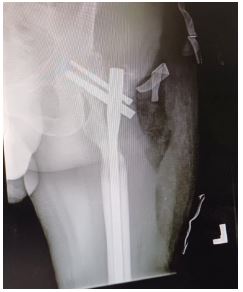

A 38-year-old male presented with a Gustilo-Anderson Grade IIIB open comminuted fracture of the left femur after a gunshot injury. The wound underwent a washout and this was followed up by ORIF using a Trochanteric Fixation Nail (TFN) (Figure 6). This was followed by primary closure of the wound and application of Vacuum-Assisted Closure (VAC) dressing. His post-operative course was uneventful and the wound healed after 18 days. The patient was allowed to mobilise with partial weight-bearing for 3 weeks followed by full weight-bearing as tolerated.

Figure 6: Anteroposterior view radiograph of the left leg showing the trochanteric fixation nail fixation.